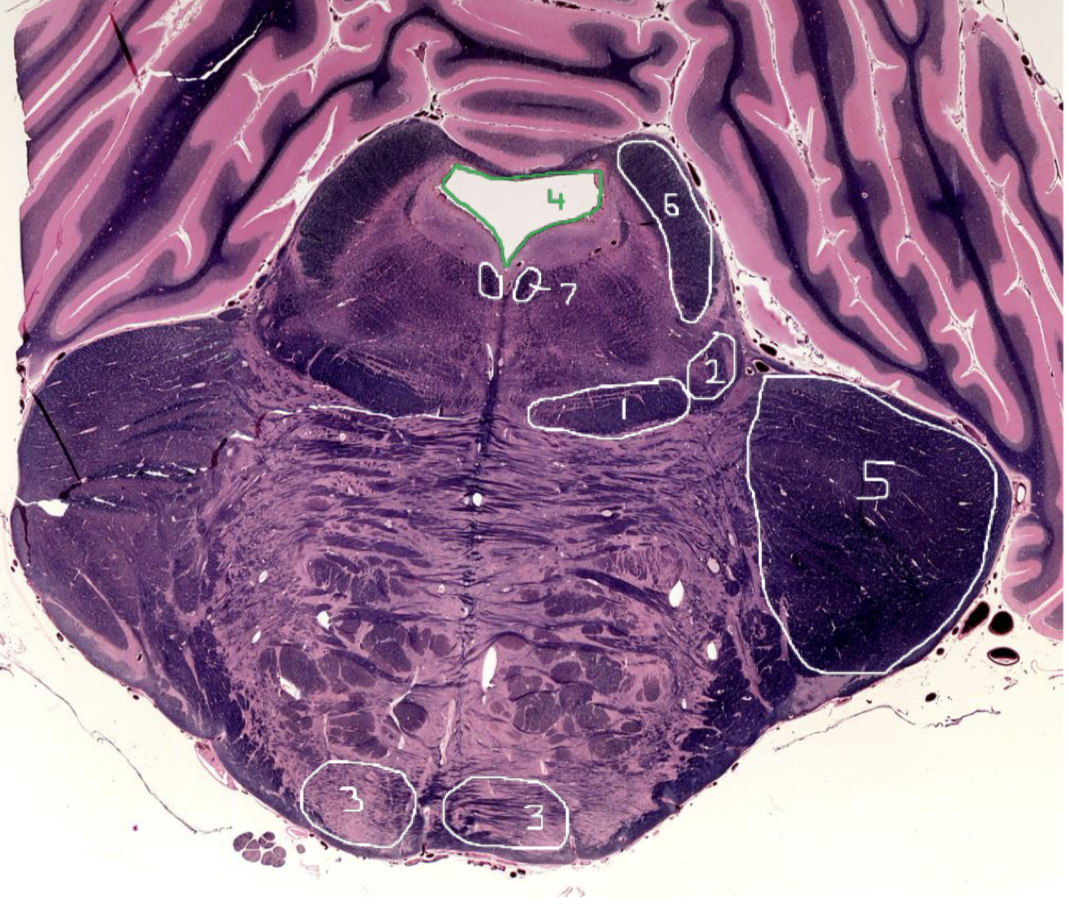

1

Medial Lemniscus - Caudal Pons

2

Spinothalamic Tract - Caudal Pons

3

CST - Caudal Pons

4

4th Ventricle - Caudal Pons

5

Inferior Cerebellar Peduncle - Caudal Pons

6

Middle Cerebellar Peduncle - Caudal Pons

7

Superior Cerebellar Peduncle - Caudal Pons

8

Dentate Nuclei (Cerebellum) - Caudal Pons

9

Inferior Olivary Nucleus - Caudal Pons

10

Medial Longitudinal Fasciculus (MLF) - Caudal Pons